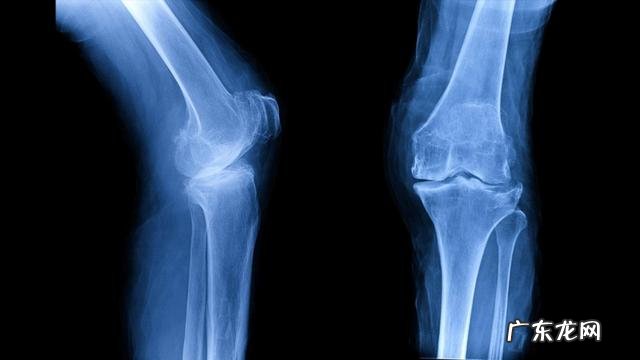

这种情况考虑她存在着严重的骨质疏松症 , 以往的四处骨折很有可能都是由于骨质疏松导致的脆性骨折 。于是给她开具了双能x线检查 , 发现重度骨质疏松 , 一般情况下进行双能x线检查 , 我们会得到一个t值 , 如果这个值低于负2.5就可以诊断为骨质疏松症了 , 但是她的t值是负3.5 , 这个差距的可不仅仅是一个1 , 这代表着大量的骨量丢失 。

通过这个病例 , 主要是想给大家介绍一下 , 很多更年期女性和绝经后女性会出现的一种骨质疏松 , 叫做绝经期骨质疏松 。其实骨质疏松就代表着体内骨骼骨量的减少 , 当我们的骨量丢失10%的时候 , 就会出现周身的疼痛 , 而且会出现肌肉与骨骼连接部位的慢性炎症 , 以及无力出汗等症状 , 当骨量丢失20%以上患者就会有明显骨折的风险 , 这种骨折叫做脆性骨折 , 其实很简单 , 就是由于骨头不再像以前那么坚强了 。